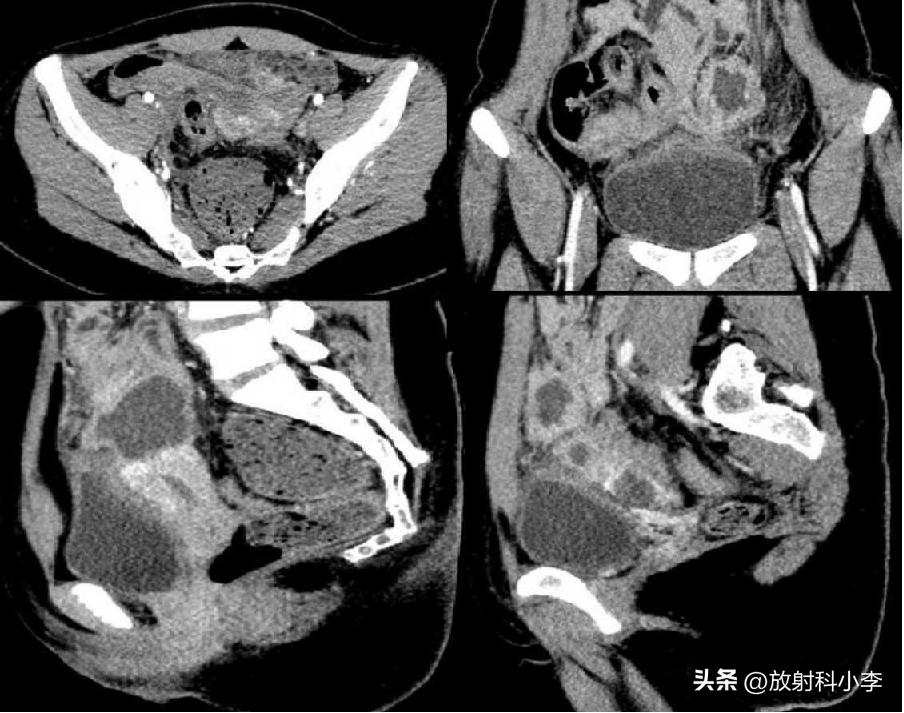

case 2. F,84Y

3年前的CT平扫示:左侧附件区肿块,主要呈实性,平扫密度较高,伴出血;3年后CT示:左侧附件区肿块较3年前明显增大,呈囊实性,实性成分为主,增强强化轻或无,瘤周见条带影/团块影与子宫相连。